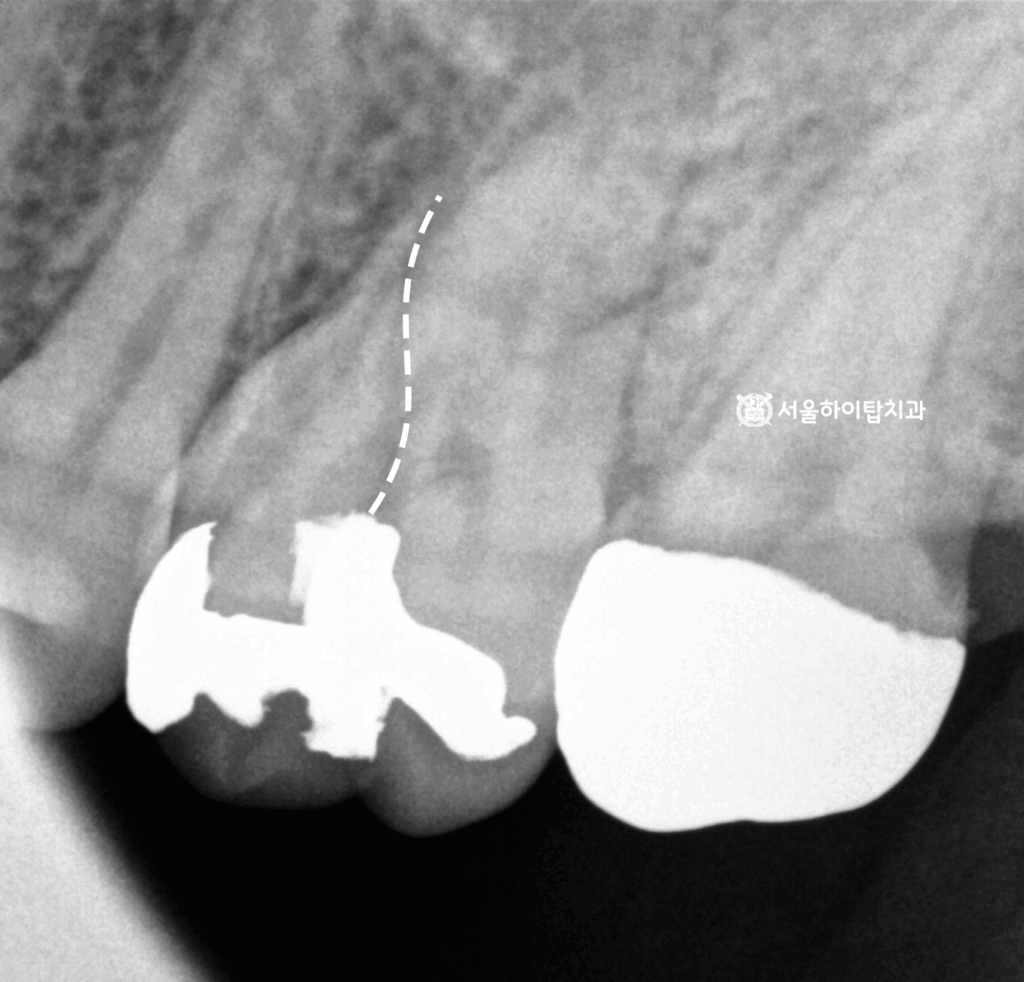

일부 파절된 어금니

만수동 치과 에서 구강 내 상태를 살펴보면,

파절된 모습이 육안으로도 확인됩니다.

이러한 경우에는 반드시

‘치근단 방사선 사진'(Periapical radiograph)을 통해

파절이 치근(뿌리) 부위까지 연장되었는지 여부를

정밀하게 평가해야 됩니다.

특히 인레이는 겉으로는 보철 파손처럼 보일 수 있으나,

실제 보철 하방의 치질이 함께 손상되었거나

파절선이 치수강 또는 치근 방향으로 확장된 경우가 존재하기 때문에

정확한 영상 진단이 필수입니다.

만약 치근부까지 파절이 도달한 경우는

수복적 치료가 불가능한 치근 파절가능성을 시사하며,

이는 예후가 불량하여 발치가 불가피한 경우도 적지 않습니다.

이에 따라 만수동 치과 에서 치근단 방사선 사진을 확인해 보면,

파절선이 치근부까지 연장된 양상을 확인할 수 있습니다.

이러한 치근 파절은 보존적 치료로 복구가 어렵고,

시간이 지날수록 염증과 골흡수를 동반하기 때문에

기능적으로 안정적인 회복을 기대하기가 어렵습니다.

따라서 파절된 치아는 발치가 필요하며,

상실된 치아의 저작 기능을 다시 확보하기 위해서는

임플란트가 가장 예후가 좋은 대체 치료로 고려됩니다.